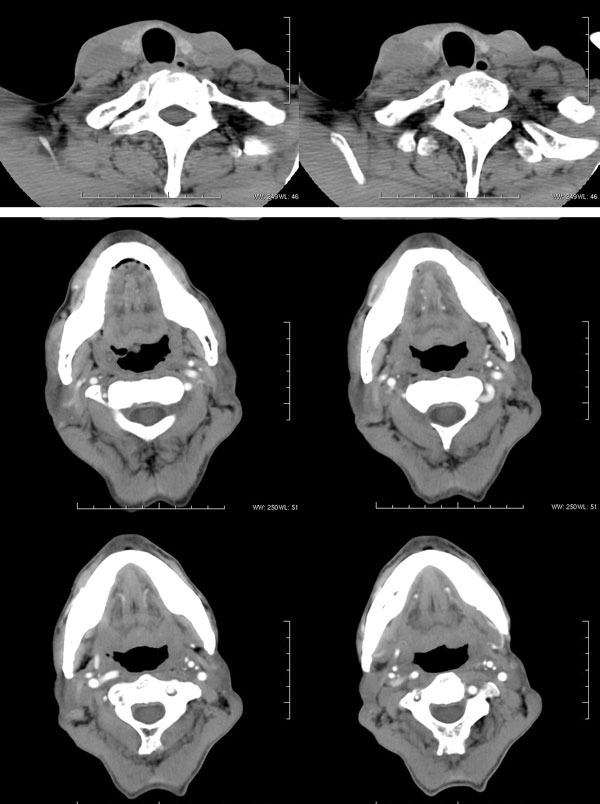

| 男性,57岁。反复声嘶1年,加重半年。 体检:喉粘膜充血,会厌肿胀,上举差,喉室及双声带窥视欠清。              蚂蚁发言:考虑喉癌(声门型)?双侧颈鞘周围淋巴结转移? 徐飞发言:有无呛水?根据病史要考虑球麻痹,脑干应检查 弯三角发言:考虑喉结核,应检查其它部位有无结核 卜一发言:喉腔右侧壁弥漫性软组织增厚,喉腔变窄。支持:喉癌(声门型)!另:双侧颈部多枚淋巴结肿大! 结果: 支纤镜检查:会厌板肿胀,右会厌咽侧壁肿胀,右杓状小结见结节样肿物,喉室肿胀,双声带肿胀、充血,左声带见菜花样肿物,触及易出血,取活检。 病理诊断:高分化鳞状细胞癌。 免疫组化:ck(h)(+++)、pcna(++)、p53(++)、ck(l)(-)。 原贴地址:http://www.radinet.com.cn/forum_view.asp?forum_id=4&view_id=34703 |